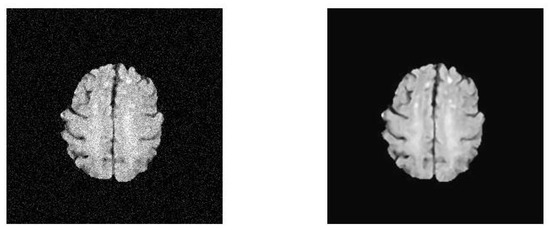

2.4.1. Discussion on MRI Brain Images

3.1. Results and Discussion of ETLFOD_model for Brain Dataset